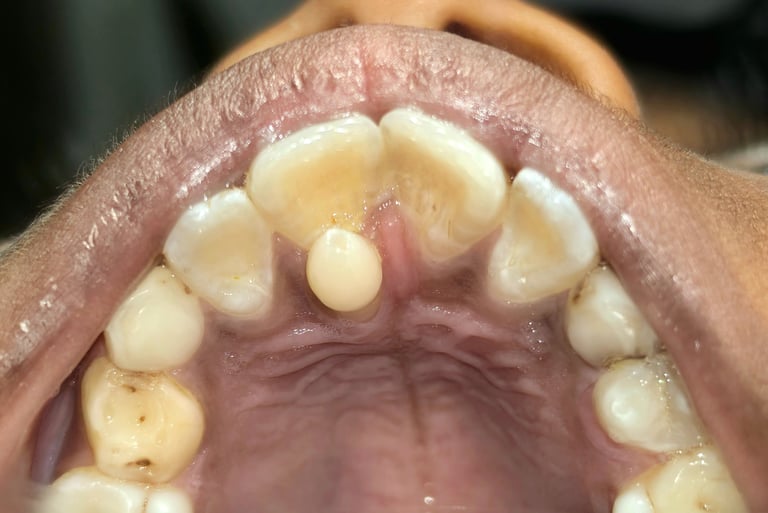

🧠 What is Mesiodens?

Mesiodens is an extra tooth that develops between the upper front teeth.

It can:

Block permanent teeth

Cause spacing or alignment issues

Affect your child’s smile and confidence

📸 Before & After Results (Conversion Booster)

Nothing builds trust like real results 💯

✔️ What You Can Expect:

Proper alignment of front teeth

Natural eruption after removal

Improved smile aesthetics